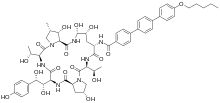

Chemistry

The present-day clinically used echinocandins are semisynthetic pneumocandins, which are chemically lipopeptide in nature, consisting of large cyclic hexapeptoids. Caspofungin, micafungin, and anidulafungin are similar cyclic hexapeptide antibiotics linked to long modified N-linked acyl fatty acid chains. The chains serve as anchors on the fungal cell membrane to facilitate antifungal activity.[9] Due to their limited oral bioavailability, echinocandins are administered through intravenous infusion.[10]